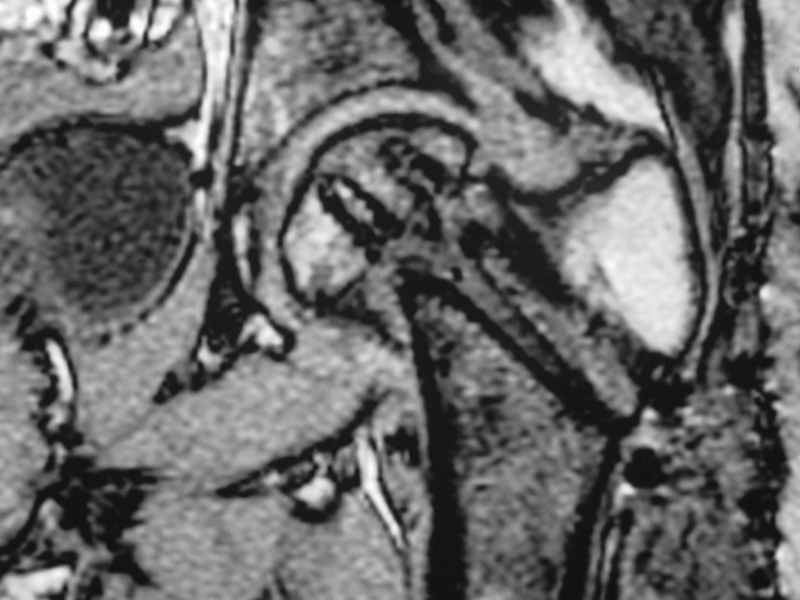

integrity consider establish vascular status via mri

and if viable follow with proximal valgus osteotomy